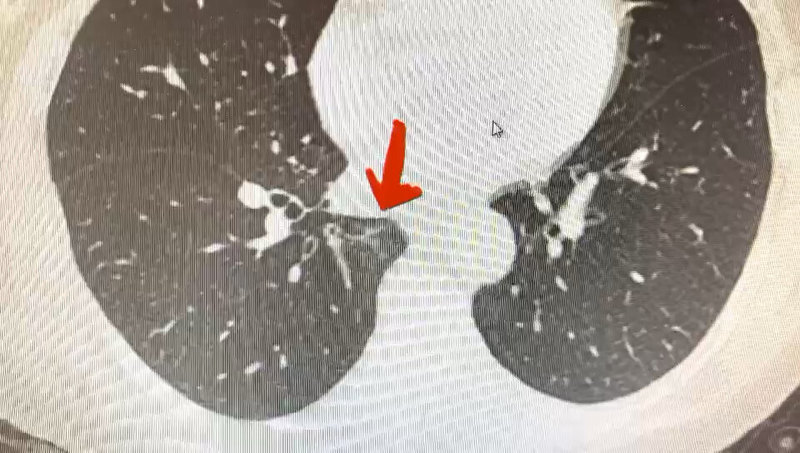

我每天在門診都可以接觸到大量的患者,帶著CT片子來就診。然而這些CT質(zhì)量參差不齊,片子的數(shù)量非常有限,通常是5毫米層厚。對于一個比較小的結(jié)節(jié)來說,很難看清他的細節(jié),因此很難根據(jù)這樣的CT做出一個準(zhǔn)確的判斷。所以我推薦所有來看我門診的患者,最好帶著CT的原始資料。例如U盤或者光盤,有些醫(yī)院可以提供二維碼。